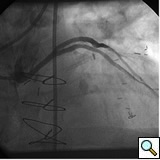

PCI of the vein and arterial grafts have unique challenges. For any PCI, guide support is very important for successful balloon and stent delivery. In a tortuous vein graft with a steep angle, advancement of a stent can be very difficult and challenging. Therefore, it is important to choose the best available catheter before starting PCI. Similar to the right coronary angiography, a JR4 guide catheter is most commonly used in this setting. However, Amplatz guide catheters for left vein grafts and multipurpose catheters for right vein grafts are better choices in certain anatomy. In Figure 8 and Figure 10 two examples of poor guide support in two vein graft interventions can be seen. Initially, a JR4 guide was used for PCI of the vein graft supplying the left anterior descending artery (LAD) without any success. However, after changing the guide to an Amplatz left 2 guide catheter, we achieved excellent support without any difficulty in advancing two stents (Figure 9). In Figure 10, difficulty is illustrated in engaging the vein graft ostium supplying the right coronary artery with a JR4 catheter. This vein graft has a very steep inferior take off from the aorta. After changing the guide to a multipurpose catheter, we were able to deliver three stents successfully without any difficulties (Figure 11). Similar challenges exist in the treatment of the left IMA or right IMA. These arterial grafts can be extremely tortuous making stent delivery very difficult. It may be necessary to use short length stents for a better deliverability or stents with lowest profile. Usually, similar to the native coronary intervention, a 6 French guide is appropriate for the routine use.

In order to minimize distal embolization, primary stenting without previous angioplasty is recommended in vein graft interventions. However, in angulated and very high grade lesions, stent without balloon angioplasty may not be able to cross a lesion requiring balloon angioplasty before stenting. Balloons should be sized smaller in order to prevent rupture or dissection. Once an angioplasty balloon is advanced across the lesion, usually it is inflated to 6 or 8 atmospheres for few seconds. Stenting is similar to the balloon. Once a stent is placed across the lesion, it is inflated to higher pressures such as 12-14 atmospheres. The use of a bare metal or drug eluting stents in vein grafts is controversy. This topic is discussed in detail in the restenosis chapter. Angioplasty and stenting of bifurcation sequential vein grafts at the site of the bifurcation or distal to the graft is challenging and usually requires more complex interventions including double wiring and utilization of two stents. A comprehensive classification with guide to interventional techniques for bifurcation lesions is published recently that can be used as a guide for bifurcation lesions interventions involving vein grafts [1].